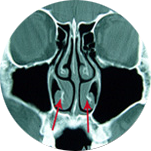

img

ºñÈļº ºñ¿°

ÄÚ ³»½Ã°æ ¼Ò°ß

ÄÚ CT ¼Ò°ß